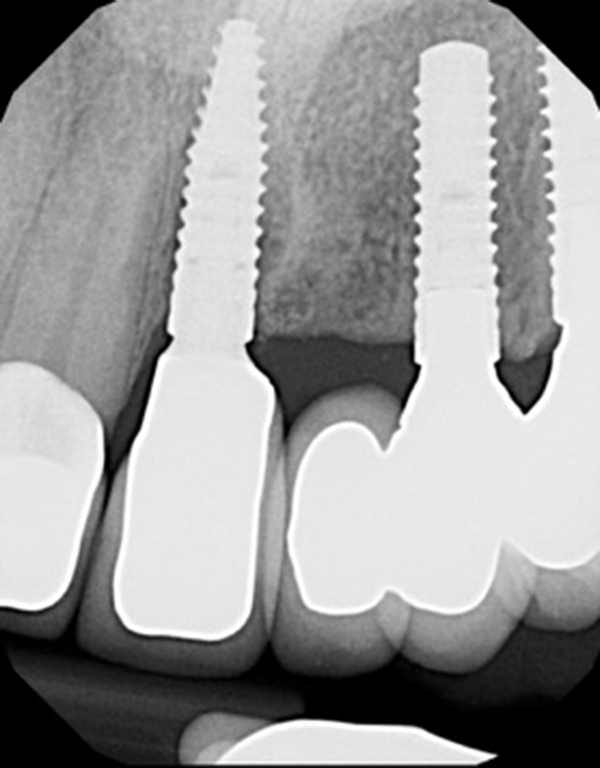

The straumann bone level tapered blt implant offers all the clinically proven features of the straumann bone level implant line plus the advantages of a tapered implant body. The cylindrical parallel outer contour allows for flexible coronal apical implant placement making it the implant of choice for esthetic sites. Bone level tapered implants blt bone level x implants blx tissue level implants. The magic behind the implant the new tapered standard.

This leads to excellent primary stability in soft bone and fresh extraction sockets. Blt tapers towards the apex coronal portion of the blt is parallel walled similar to the bl implant the benefits of bl implant apply to blt implant blt key features and benefits hybrid design.